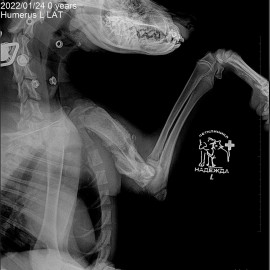

Наш пациент пёс по кличке Малыш. Обратились к нам в клинику с жалобами на хромоту на переднюю левую лапу. Был проведен осмотр и рентгенологическое исследование, после которого был поставлен диагноз: состояние после перелома левой плечевой кости. Была проведена операция: остеосинтез левой плечевой кости.

Снимок 3-4 после операции.